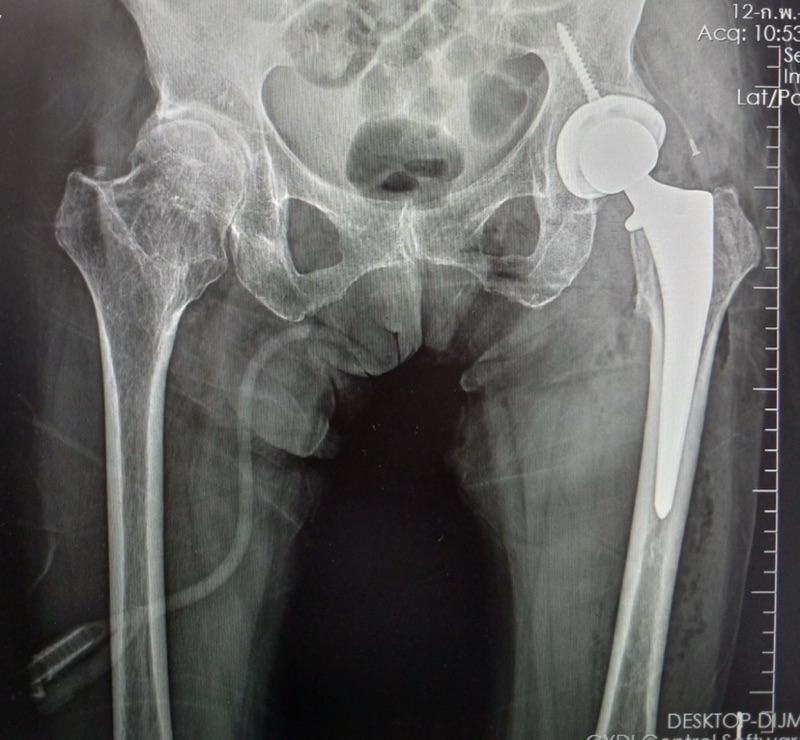

การผ่าตัดเปลี่ยนข้อสะโพก (Hip Replacement Surgery) เป็นการนำ กระดูกสะโพกส่วนที่หักออกและแทนที่ด้วยข้อสะโพกเทียม ซึ่งทำจากโลหะหรือเซรามิก เพื่อให้ผู้ป่วยสามารถกลับมาเดินได้อีกครั้ง

1️⃣ เปลี่ยนบางส่วน (Hemiarthroplasty) – เปลี่ยนเฉพาะหัวกระดูกต้นขา เหมาะสำหรับผู้สูงอายุที่ไม่ต้องการใช้งานหนัก

2️⃣ เปลี่ยนทั้งหมด (Total Hip Replacement - THR) – เปลี่ยนทั้งหัวกระดูกและเบ้าสะโพก ช่วยให้เคลื่อนไหวได้ดีขึ้น